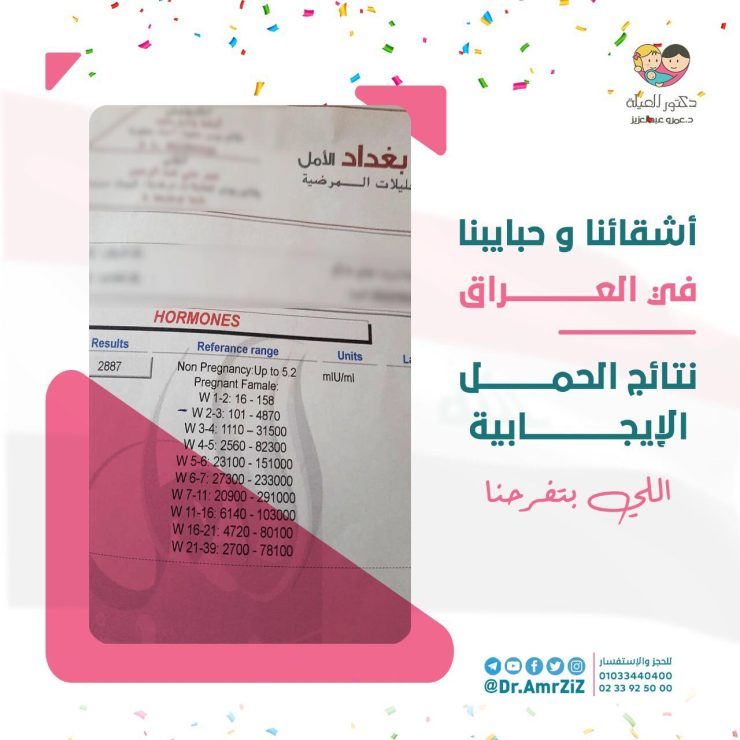

تواصلت السيدة “إلهام” مع عيادة د.عمرو عبدالعزيز وتم حجز أقرب ميعاد لها، وعند قدوم موعد الاستشارة مع د.عمرو عبدالعزيز خضعت السيدة “إلهام” لفحوصات دقيقة تحت إشرافه، وتم التأكد من إصابتها بمرض بطانة الرحم المهاجرة بناءًا على نتائج الفحوصات والتحاليل الطبية، بعد ذلك قام د.عمرو عبدالعزيز بوضع خطة علاجية مناسبة لمشكلة بطانة الرحم المهاجرة التي تعاني منها السيدة “إلهام”، والتي شملت على العلاج بالأدوية الهرمونية وبعض الأدوية المسكنة للألم، بالإضافة إلى بعض التغيرات في نمط الحياة.

بعد تحسن حالة السيدة “إلهام” وتحكمها في أعراض بطانة الرحم المهاجرة، تكللت رحلتها العلاجية بالنجاح، فقد حملت بعد عملية الحقن المجهري، و عاشت السيدة “إلهام” أجمل مشاعر الأمومة مع مولودها الجديد “يونس”، بعد سنوات من الانتظار والمعاناة.